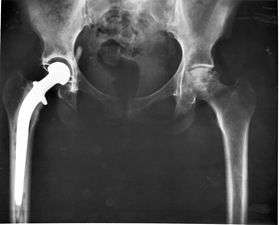

X-ray of a hip replacement.

The modern total hip replacement was pioneered by Sir John Charnley, expert in tribology at Wrightington Hospital, England in the 1960s.[8] He found that joint surfaces could be replaced by implants cemented to the bone. His design consisted of a stainless steel one-piece femoral stem and head and a polyethylene, acetabular component, both of which were fixed to the bone using PMMA (acrylic) bone cement. For over two decades, the Charnley Low Friction Arthroplasty and its derivative designs were the most-used systems in the world. This formed the basis for all modern hip implants.

The Exeter hip replacement system (with a slightly different stem geometry) was developed at the same time.Since Charnley, there have been continuous improvements in the design and technique of joint replacement (arthroplasty) with many contributors, including W. H. Harris, the son of R. I. Harris, whose team at Harvard pioneered uncemented arthroplasty techniques with the bone bonding directly to the implant.